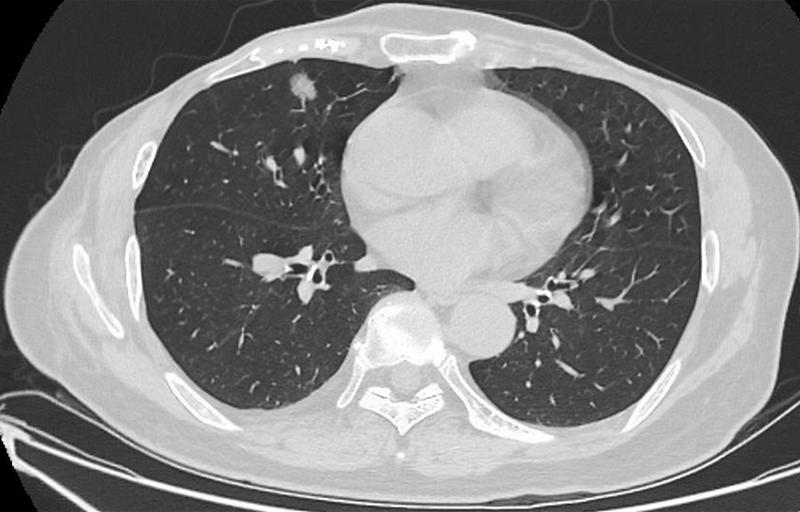

肺結(jié)節(jié)是指肺部出現(xiàn)的直徑小于3厘米的圓形或類圓形病灶,大多數(shù)肺結(jié)節(jié)是良性的,但部分可能需要治療,肺結(jié)節(jié)的癥狀因個體差異而異,部分患者在早期可能無任何癥狀,因此定期進行體檢至關(guān)重要。